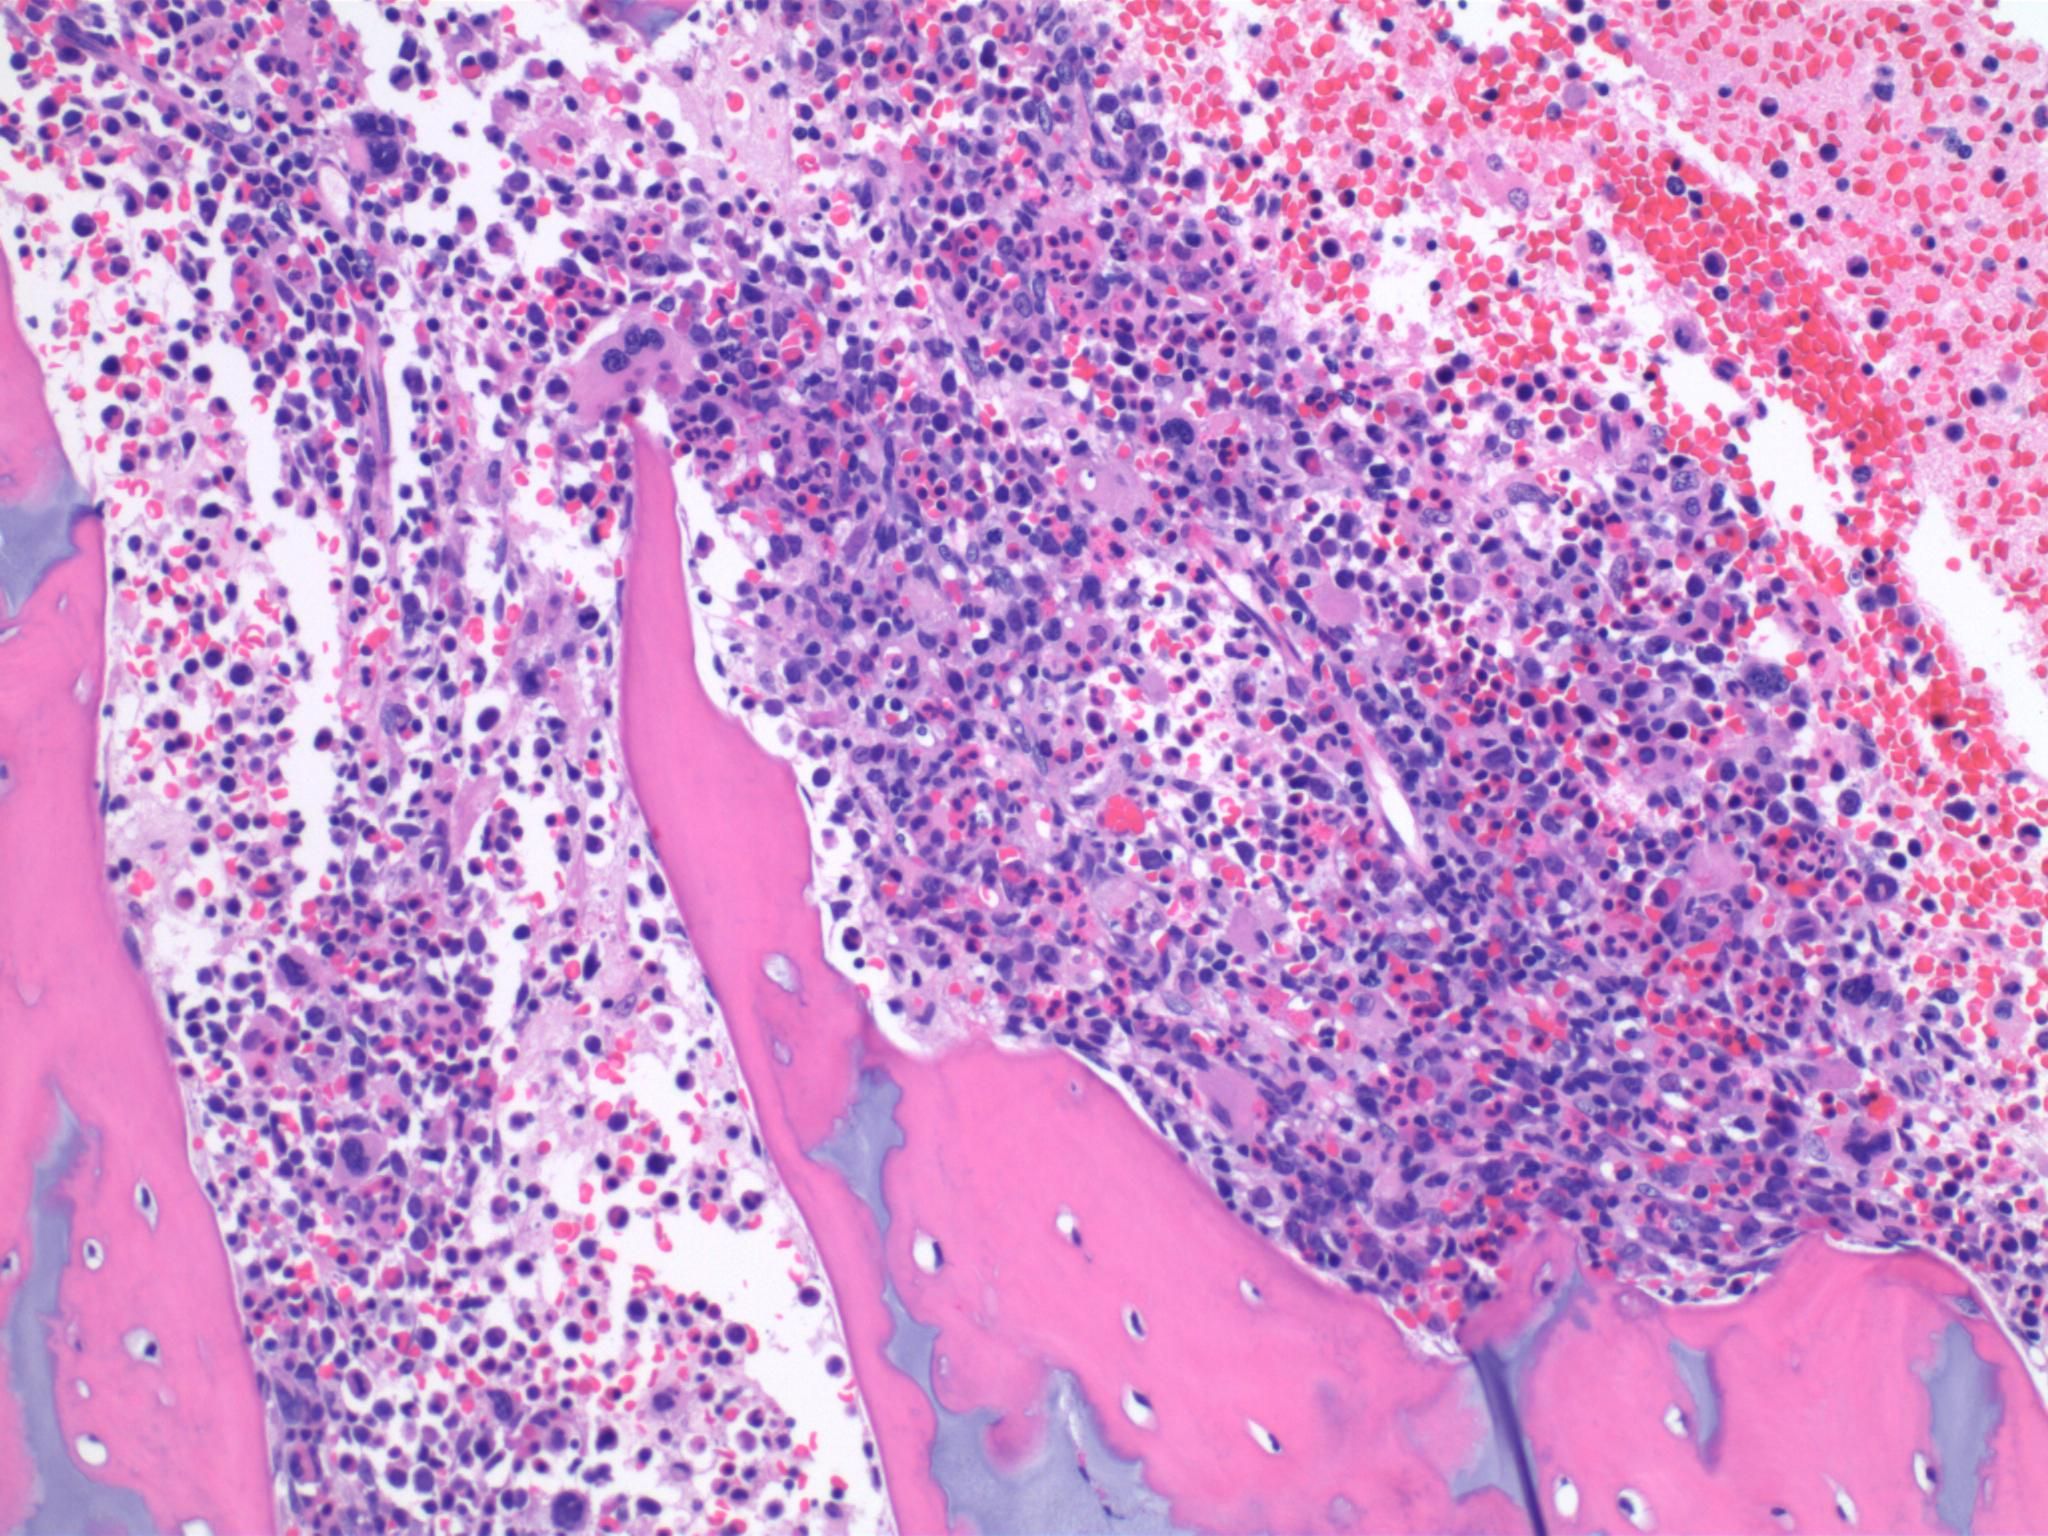

Laboratory evaluation showed transaminitis with ALT of 325 Units/L (normal 5-45 Units/L), AST of 393 Units/L (normal 20-60 Units/L), total bilirubin of 3.4 mg/dL(normal 0.2-1.3 mg/dL) with direct bilirubin of 0.7mg/dL (normal 0.0-0.3 mg/dL), decreased albumin of 3.1 (normal 3.4-4.2g/dL), and lactate dehydrogenase and D-dimer were significantly elevated at 2007 Units/L (normal 500-920 Units/L) and 15,099 ng/ml (normal 215-500ng/ml) respectively. White blood cell count revealed pancytopenia with WBC count of 3.34x10^9/L (normal 7.7-13.7x10^9/L), RBC count of 2.65x10^6/L (normal 3.0-4.3x10^6 L), Hgb of 8.1g/dL (normal 9.5-13.3g/dL), platelet count of 56x10^9/L (normal 150-500x10^9L). Differential count showed 22.1% neutrophils, 54.5% lymphocytes, 19.8% monocytes, 0.3% basophils, 0.3% eosinophils and 3% immature granulocytes. Reticulocyte count was mildly elevated at 5.43% (normal 0.90-3.80%). PT was elevated at 13.3 seconds (normal 9.6-12.5 seconds). Blood, urine and cerebrospinal fluid cultures were all negative. Triglycerides were normal at 118mg/dL (normal 40-160mg/dL), and all other labs were without significant abnormality. CXR was normal. Repeat head CT confirmed previously described skull fracture without intracranial hemorrhage. Abdominal ultrasound showed splenomegaly without hepatomegaly. Continued investigation over the next week included consultations from oncology and infectious disease services. Additional testing revealed elevated serum ferritin of 11,100ng/mL (normal 14-647ng/ml) and soluble CD-25 of 79,500pg/ml (normal 0-1033pg/mL). Histopathology of a bone marrow biopsy revealed mild histiocytic hyperplasia with increase in histiocytes with occasional hemophagocytosis. Epstein Barr Virus was positive by in situ hybridization (Figure 1: Images A-D).